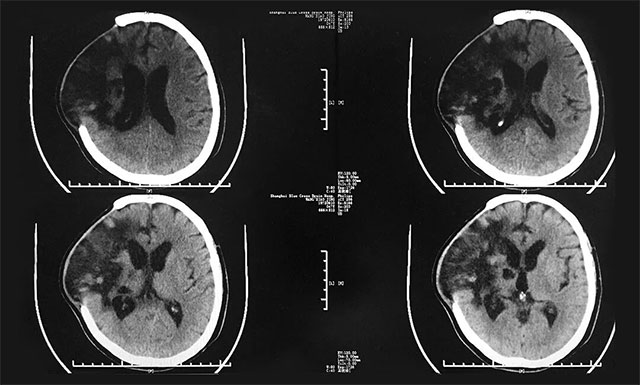

據(jù)患者丈夫回憶,去年12月14日,張女士在健身房做完運動后突發(fā)腦出血而昏迷不醒,之后被120送往上海某醫(yī)院進行救治,并初步確診為右側(cè)額顳葉腦出血。因其腦出血量比較大,約為80毫升,于急診先后進行了右顳腦內(nèi)血腫清除術(shù),顱內(nèi)壓監(jiān)護探頭置入術(shù)以及去骨瓣減壓術(shù),經(jīng)過治療,患者病情基本穩(wěn)定,但仍處于昏迷狀態(tài),家人很是擔心,F(xiàn)為求進一步治療,患者慕名就診于上海藍十字腦科醫(yī)院。

▲ 入院前,患者腦部感染嚴重

入院后,潘仁龍主任對患者進行了全面而細致的檢查,并針對其之前腦出血的情況予以營養(yǎng)神經(jīng)、改善微循環(huán)、促醒、抗感染、補液等對癥治療;同時,還邀請康復科專家、高壓氧科專家及中醫(yī)科專家分別進行會診,并給予相應(yīng)輔助治療,之后患者情況較前有所好轉(zhuǎn),GCS評分也從之前5分變?yōu)?分(E4分、V1分、M3分)。